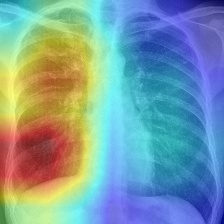

Figure 3: Result attribution heatmaps for mammography [17] and chest X-ray [14]: (a) original image overlayed with annotation contours (and arrows for missing GT), (b) our attribution framework. (c) GradCAM [25] (d) Saliency [26].

Attribution: We compared our attribution network against the gradient explanation saliency map [26] (SAL), and the network/gradient-derived GradCAM [25] visualizations. We limited our comparisons to these direct approaches, as they are widely used within medical imaging [13], and inherently valid [2]. Popular reference based approaches either utilize blurring, noise or some other heuristic [9, 8, 31], or were not available [7], therefore could not be considered. Quantitatively, we relate (i) the result-maps M^^𝑀\hat{M} to both organ, and ground truth (GT) annotations, and (ii) to each other. Particularly for (i) we studied the Hausdorff distances H𝐻H between GT and M^^𝑀\hat{M} indicating location proximity. Lower values demonstrate better localization in respect to the pathology. Further, we performed a weak localization experiment [8, 9]: per image, we derived bounding boxes (BB) for each connected component of GT and M^^𝑀\hat{M} attributions. A GT BB counts as found, if any M^^𝑀\hat{M} BB has an IOU 0.125absent0.125\leq 0.125. We chose this threshold, as a proficient classifier presumably focuses on the masses’ boundaries and neighborhoods, thereby limiting possible BB-overlap. We report average localization L𝐿L. For (ii) we derived the area ratio A𝐴A between M^^𝑀\hat{M} and organ-mask (breast-area) or whole image (chest X-ray). Again, lower values indicate a smaller thereby clearer map. Due to missing GT we could only derive (ii) for TBC. All measurements were performed on binary masks, hence GradCAM and SAL had to be thresholded. We chose the 50,75,9050759050,75,90 percentiles, i.e. compared 50,25,1050251050,25,10 percent of the map-points. Where multiple pathologies, or mapping results occurred we used the median for a robust estimation per image. Statistically significant difference between all resulting findings was formalized using Wilcoxon signed-rank tests, for α<0.05𝛼0.05\alpha<0.05. Additionally we followed [2], and tested our network with randomised parametrization (labels have no effect in our case).

As seen in Table 1, our framework achieves significantly lower H𝐻H, than either GradCAM or SAL at all threshold levels. Moreover, we report significantly better weak localization (L𝐿L) which underlines the higher accuracy of our approach. Qualitatively our attribution-maps are tighter focused (c.f. Fig. 3(b)) and enclose the masses. The former is also expressed by the lower overlap values A𝐴A. All p-values where significantly below 1e-21e-21\text{e-}2, hardening our results. Randomization of the ANN’s weights yields pure noise maps, hence we pass [2]’s checks.